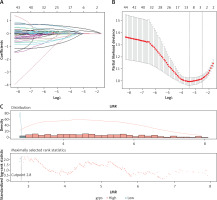

The prognosis values based on the LMR, SSIGN, and MAPS

Among the 44 variables, the risk indicators (regression coefficients) selected by LASSO Cox regression were LMR (0.025) in blood indexes; Fuhrman tumour grading, size, and SSIGN (0.062, 0.064, 0.222) on pathology; and MAPS (0.470) for images (Table III, Figures 2 A, B). The optimum cut-off value on the LMR was 2.80 (Figure 2 C), and the LMR (≥ 2.8 vs. < 2.8) was assigned points (0 or 1) to each indicator. According to the cut-offs in the literature, SSIGN (0–3 vs. 4–7 vs. 8) were assigned points (0, 1, 2), and MAPS (0–3 vs. 4–5) were assigned points (0 or 1) to each indicator [10, 18]. The Kaplan-Meier survival analysis showed that LMR, MAPS, and SSIGN have significant prognosis values in predicting DFS (p = 0.019, p < 0.0001, and p < 0.0001) (Figures 2 D–F).

Figure 2

Clinical outcomes based on LMR, SSIGN, and MAPS. A – LASSO coefficient profiles of the 44 variables; B – 10-fold cross-validation for tuning parameter selection in the LASSO model; C – The optimal cut-off value for LMR

LMR – lymphocyte to monocyte ratio, SSIGN – the Mayo Clinic Stage, size, grade, and necrosis score, MAPS – Mayo adhesive probability score, DFS – disease-free survival.